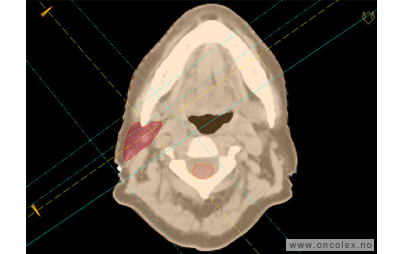

Målvolum

Skisse over hvordan strålefeltet planlegges:

Illustrasjon for målvolum

• GTV (Gross Tumor Volume): Identifisert tumor.

• CTV (Clinical Target Volume) GTV + omkringliggende vev hvor det kan væremikroskopisk spredning.

• ITV (Internal Target Volume): CTV + en indre margin som tar hensyn tilindre bevegelser og endringer av CTV.

• PTV (Planning Target Volume): Innstillingsmargin som inneholder ITV og samtidig tar hensyn til antatte pasientbevegelser, samt variasjoner i pasientopplegging og feltinnstillinger.

• Feltgrense. Tegnes som oftest på kroppen.

ICRU (International Commission on Radiation Units and Measurements)